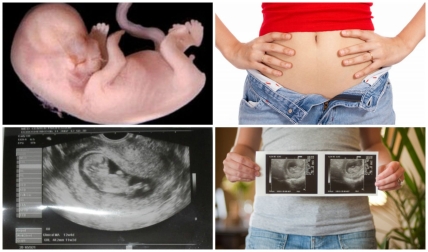

На 11 неделе беременности малыш продолжает активно расти, он становится все больше похожим на человека, его вес 8 г., а длина от крестца до темени ок.50-60 мм.

У него развился хватательный рефлекс, закладывается радужная оболочка глаз, он может чувствовать вкус окружающей его жидкости, завершается формирование грудины, диафрагмы и гениталий.

Начинает работать кишечник малыша, его печень уже производит кровь, в составе которой пока только лимфоциты, которые помогают выработать иммунитет, и эритроциты, а лейкоциты появятся позже.

У ребенка укрепляется шея, и теперь он может поднимать голову, она все еще достаточно большая, по размеру почти сопоставима с телом, что объясняется необходимостью быстрого развития мозга.

: «Голова Вашего будущего ребенка составляет половину длины тела, и эта диспропорция останется и после родов. Глаза широко расставлены, уши расположены низко, ноги коротки по сравнению с телом. На 11-той неделе печень составляет 10% веса ребенка. Начинают функционировать почки – производят мочу. Эта моча пополняет объем околоплодной жидкости. Отработанные продукты передаются через плаценту в кровеносное русло и выводите из организма их уже Вы. Рост плода 6 см, вес 8 г, размером с абрикос. Малыш начинает поднимать голову. Постепенно развивается и укрепляется шея. Матка начинает увеличиваться пропорционально росту плода в ней. Она уже заполняет собой почти всю область малого таза.